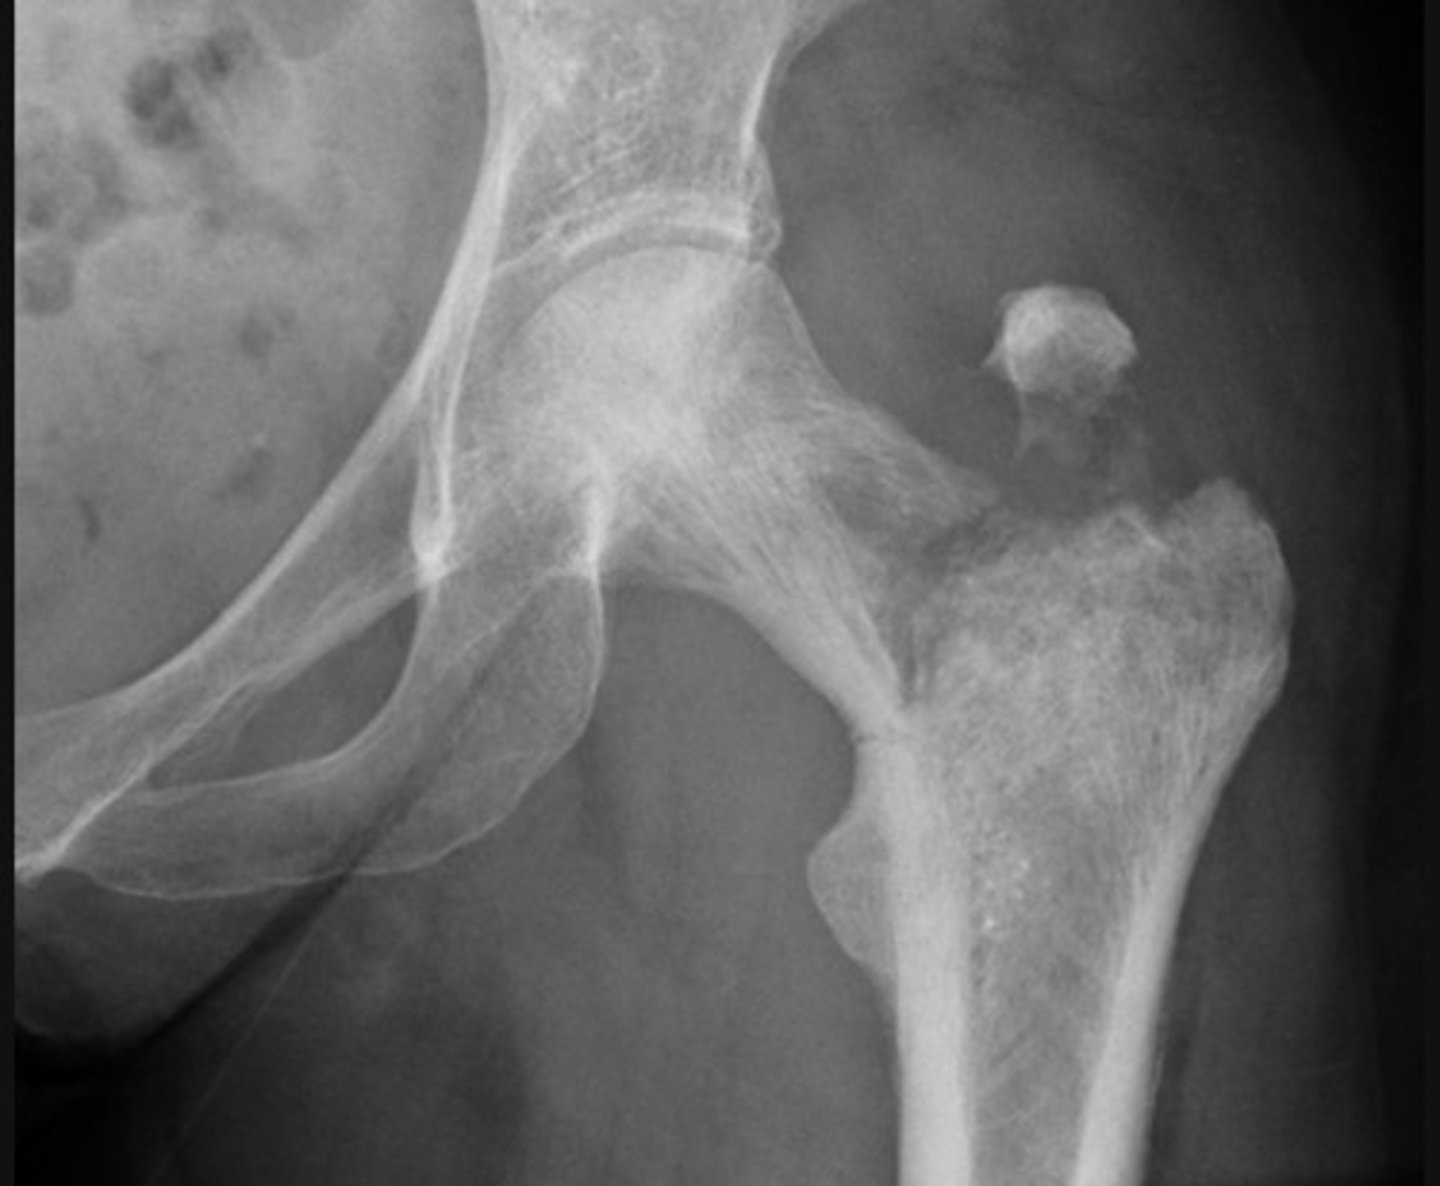

Subcapital fracture with complete displacement

Transcervical fracture with minor displacement

A fracture of the femoral neck is accompanied by avulsion of the greater trochanter